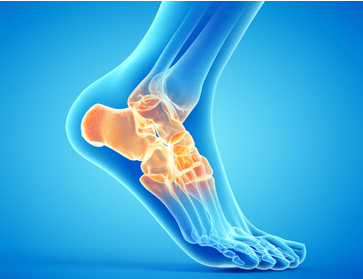

Foot & Ankle